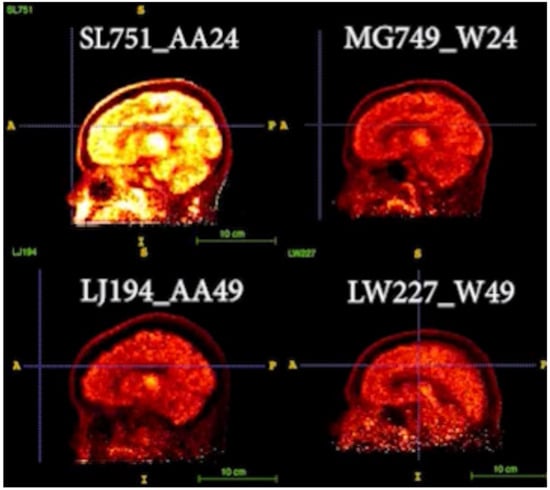

In addition to standardized lateral cephalometric radiographs, comprehensive assessment using dental cone-beam computed tomography (CBCT) and CT has become commonplace in the diagnosis and treatment of jaw deformities. Simulation based on cephalometr...